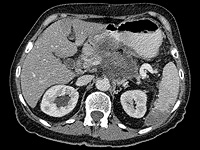

В Европе от донора спермы с генной мутацией, приводящей к раку, были зачаты 200 детей

Донор спермы с генной мутацией, радикально повышающей риск развития рака, стал отцом 200 детей по всей Европе. Это выяснилось в ходе масштабного расследования, проведенного крупными вещателями, включая CBS News, BBC News.